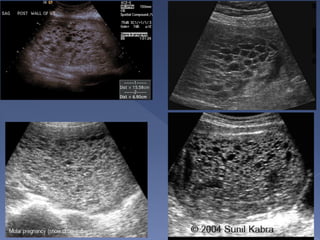

 Clinical presentation

 Snow storm

appearance

 Very High BHCG

 Theca lutein cysts in

both ovaries

 Always check

pathology

 The ovaries are commonly the site for theca lutein

cysts secondary to the BHCG.